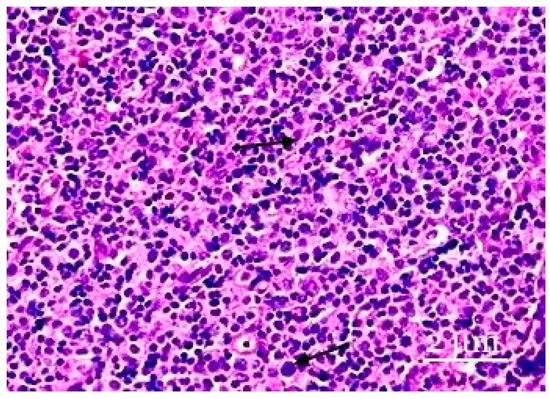

This paper provides data regarding the ratios of the functional structures of lymph nodes after inflammation in the abdominal organs. Lymph systems, including lymph nodes, function as filters of tissues and tissue fluids and are places of origin and lymphocyte production for normal [...] Read more.

This paper provides data regarding the ratios of the functional structures of lymph nodes after inflammation in the abdominal organs. Lymph systems, including lymph nodes, function as filters of tissues and tissue fluids and are places of origin and lymphocyte production for normal physiological functions. They display specific morphological and functional responses in reaction to endogenous and exogenous substances. The morphological pattern of the mesenteric lymph node in experimental rat groups reflects a decrease in its immune function due to the processes of inflammation in the abdominal cavity. These processes work together with the associated organs and their involvement in the abdominal lymph nodes, in which there are discharges of the structure of the paracortical zone under conditions of reduced lymphogenic processes, according to the decrease in the size of the paracortex and the ratios of lymphoid nodes with and without germinal centers. Histological and morphometric analyses show changes in the mesenteric lymph node. These analyses are characterized by changes in the cortical and medullary substances, while the proportion of the cortical structure decreases. We also noted an increase in the number of macrophages in the lymphoid nodes and cerebral sinus, as well as a decrease in the number of mature plasmocytes, the paracortex, and the pulp strands. These changes indicate immunosuppressive effects on the lymph node. Under the conditions of inflammation, the formation of a mixed immune response occurs. Full article